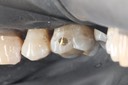

Wayne Chin #12 pre-op

Wayne Chin #12 amalgam removal

Wayne Chin #12 prep